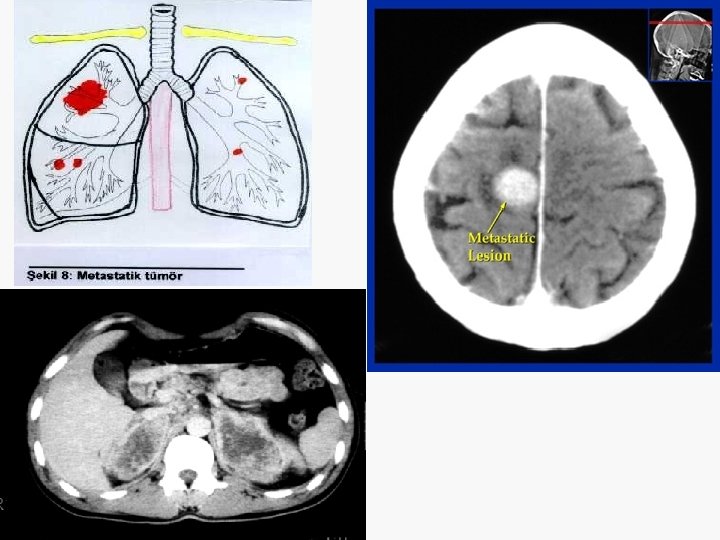

En sık metastaz yerleri Kemik Karaciğer Sürrenal Beyin Karşı akciğer